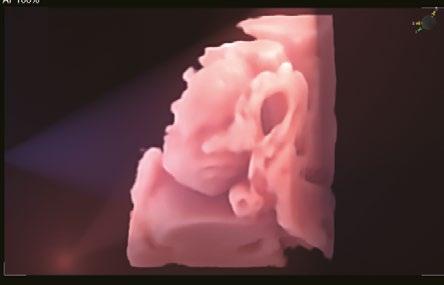

Eine neue 3D-Rendering-Technologie, die es dem Benutzer ermöglicht, die Position und Richtung der virtuellen Lichtquellen individuell anzupassen, wodurch die Details der inneren Strukturen deutlicher dargestellt und die dreidimensionale Wahrnehmung verbessert werden.

Color 3D-Rendering-Technologie für eine verbesserte 3D Visualisierung und Strukturdarstellung, z.B. bei der Nabelschnur.